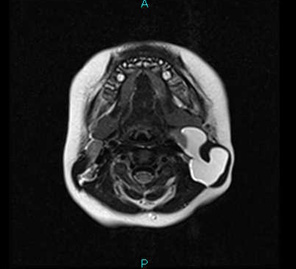

がま腫とは、舌下腺や唾液管が何らかの刺激で損傷をうけることで、そこから唾液が外に漏れ、やがてその周囲に膜ができ袋状になったものです。実際取り出すと、うすい膜でおおわれた半透明の袋をしています。中には唾液が溜まっています。(→がま腫)

通常口の中の底、舌の付け根にできます。口を開けたときに見ることができます。ときには、口の底の筋肉のすき間から、顎の下方にはみ出るような形でできることがあります。こういうケースでは、一見正中頸嚢胞のような、顎の下に袋がみられることがあります。